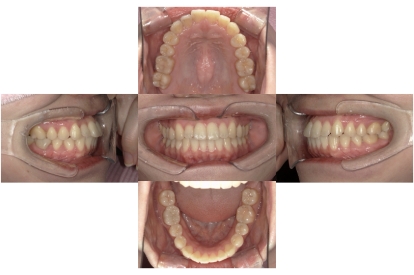

BEFORE

AFTER

上下顎叢生、上顎前突(出っ歯、上下の前歯のガタガタ)のケースです。

装置はラビアル(上下表側)で、上顎の小臼歯を2本抜歯を行っています。抜歯したスペースを使って、上の前歯の後方移動と叢生(ガタガタ)と出っ歯の改善を行っています。下は歯と歯の間にIPR(隣接面削合)を行い、スペースを確保し、叢生の改善を行っています。

主訴 前歯のガタガタと出っ歯が気になる。

年齢・性別 47歳 女性

お住まいの地域 神奈川県川崎市

治療方針 抜歯スペースおよびIPRを利用して上前歯の叢生(ガタガタ)の改善

抜歯部位 上顎左右第一小臼歯

使用装置 ラビアル(上下表側)、顎間ゴム

治療期間 2年0か月

治療回数 15回

リテーナー クリアリテーナー